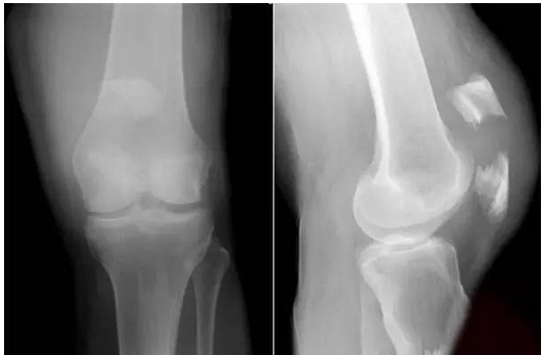

日走3万步,断了大腿骨!

一位60多岁的病人,这位病人体重60公斤,身高一米六,每天暴走15公里。刚开始锻炼有点腰酸背痛也正常,但走了半个月以后,一站起来就觉得右边大腿根部疼痛,当时还可以走路,就以为是扭伤了,撑着没到医院去。后来,越来越疼,病人才到医院,一检查才发现,原来是大腿的骨头“走断了”......